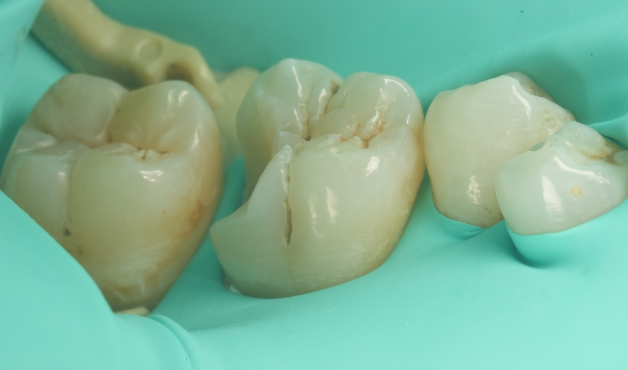

通常インレーになる二次カリエスの歯を

最小限の治療で修復した症例

Before

After

主訴

銀歯が外れたところを長持ちする方法で治療して欲しい

治療内容

ダイレクトレストレーション

治療費用

55,000

治療の

リスク

治療直後(24時間以内)に硬いものを噛むと知覚過敏症状が生じる可能性があります。